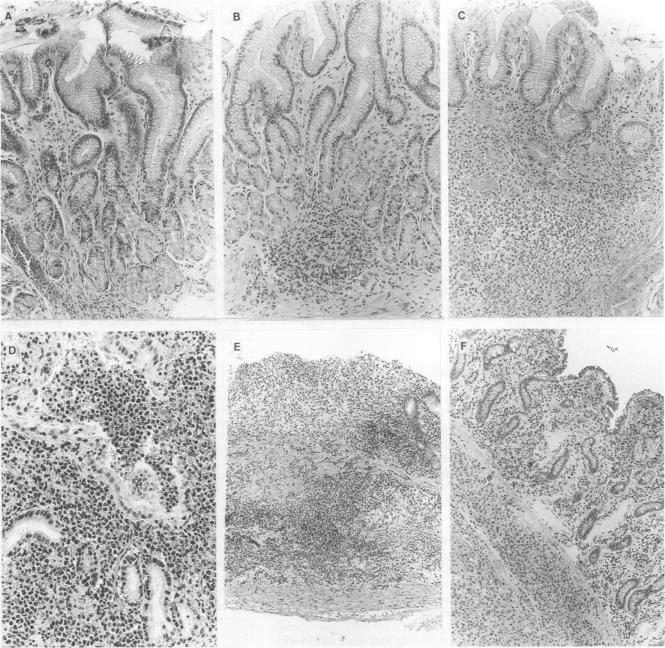

To determine the prevalence of mucosa associated lymphoid tissue (MALT) in the stomach and of a possible antigen driven proliferation, in patients with Sjögren's syndrome (SS).

Twenty one patients with primary SS and 80 dyspeptic controls underwent upper endoscopy. Lymphoid tissue and Helicobacter pylori were assessed by histopathological analysis. Epstein-Barr virus (EBV) or human herpes virus-6 (HHV-6) genome were studied by polymerase chain reaction (PCR) DNA amplification. Two PCR VDJ procedures were used to detect immunoglobulin heavy chain (IgH) gene rearrangement.

Organised MALT was found in 33.3% of the patients, compared with 21.5% of the controls (NS). H pylori infection was seen in 71% of patients and 63% of controls. Genomic EBV or HHV-6 was found in a minor portion of SS gastric tissues. B cell expansion was detected in nine of the 21 patients. Infectious agents in the stomach might have contributed to B cell clonality only in 55.5% of the cases. No strict relationship was found between lymphoid follicles and clonality.

Lymphoid accumulation in the gastric mucosa is common in Sjögren's syndrome, but full evidence for an antigen driven B cell expansion could not be demonstrated. Only a portion of those with clonal B cell expansion had evidence of an infectious agent. Other unknown infectious agents or factors related to the underlying disease (autoantigen) and its tissue environment may have a further role as possible causes of B clonal expansion in the gastric mucosa.